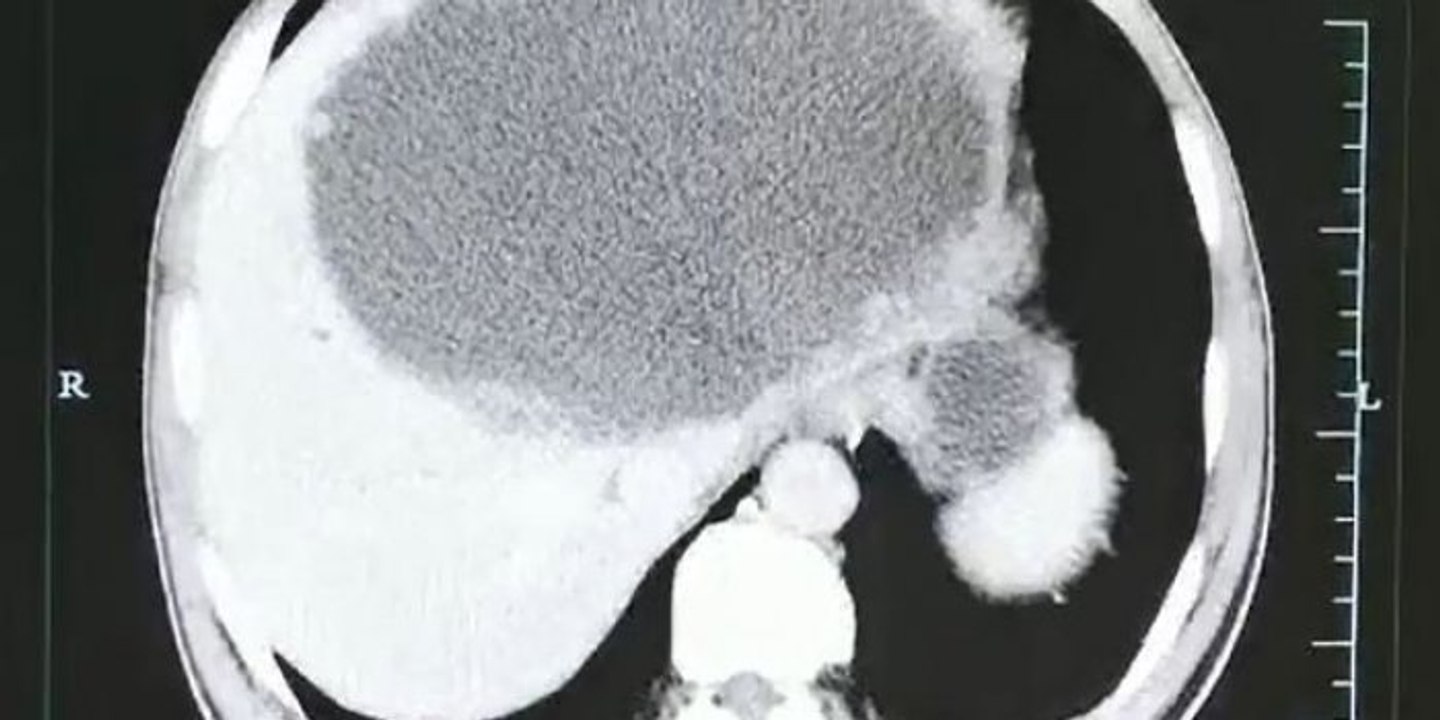

Après avoir mangé du poisson cru, il a eu le foie infesté de vers 0:31

Après avoir mangé du poisson cru, il a eu le foie infes...

Le Tribunal Du Net 4.9K views